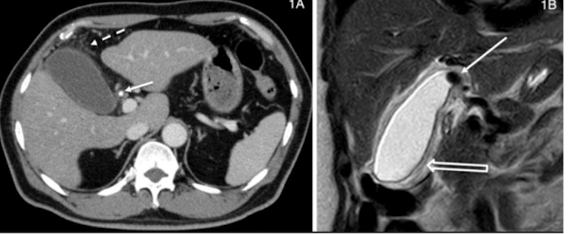

What is this and what type of scan

Cholecystitis, CT